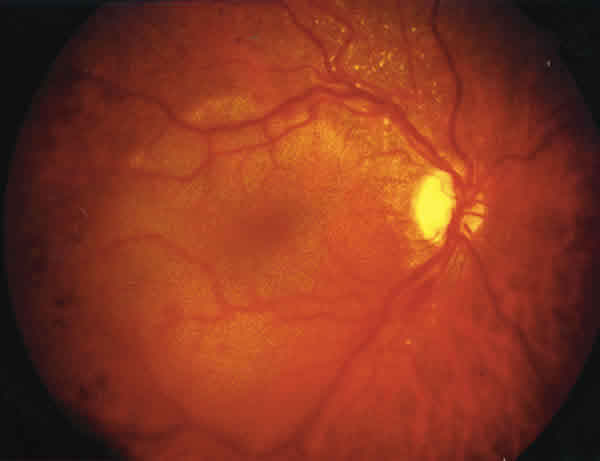

f07-07.jpg (9429 bytes)

Fig. 7.

Caso 2: Retinografía OI. Dilatación venosa y hemorragias retinianas dispersas.